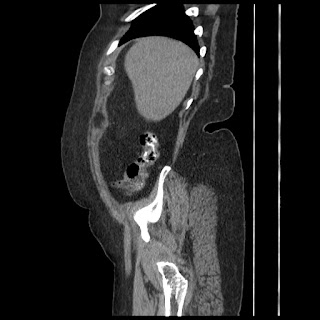

A 70 years old woman with Obstractive jaundice & palpable GB